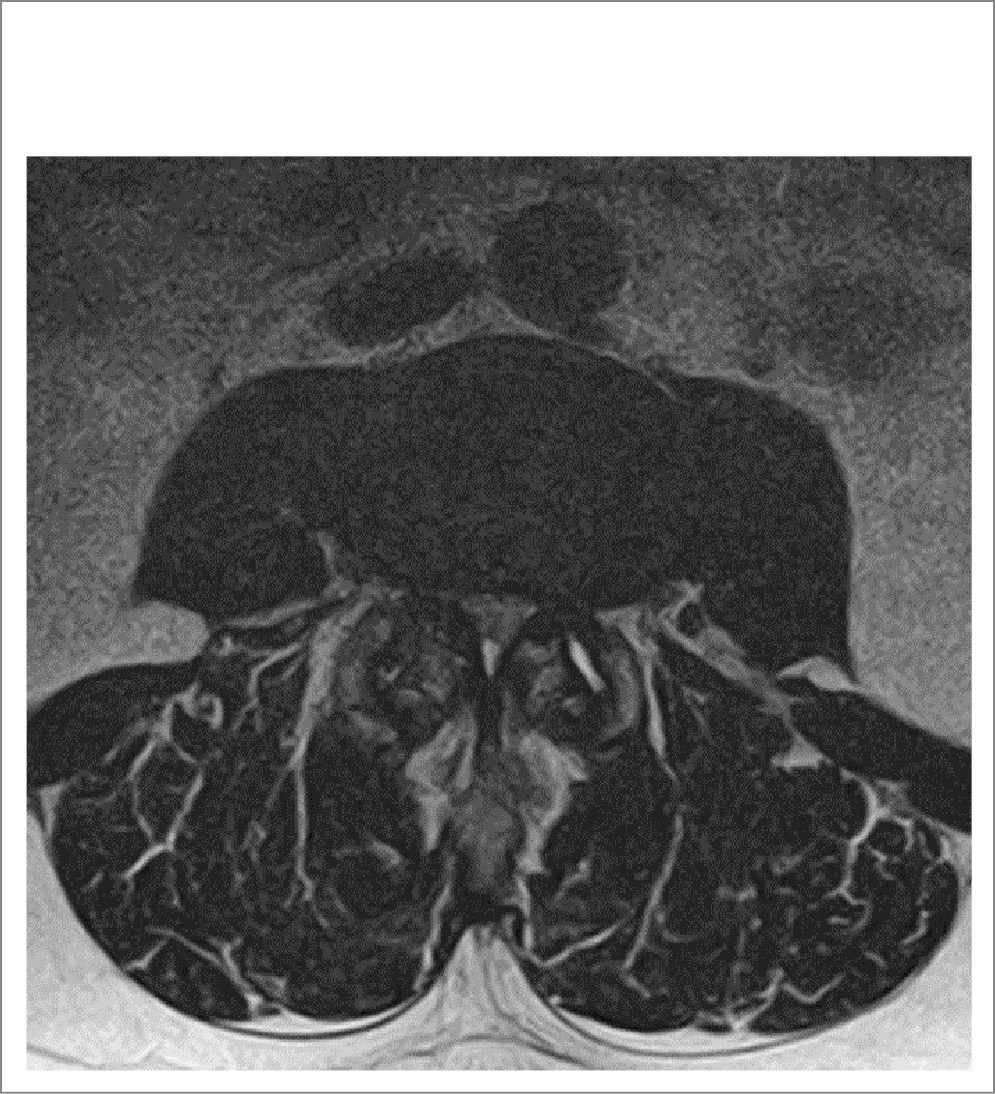

Произведены задний транспедикулярный спондилодез LII–LIII–LIV путем установки транспедикулярных металлофиксаторов (рис. 2), декомпрессивная ламинэктомия LIII (рис. 3), аркотомия LII и LIV c резекцией гипертрофированной желтой связки, медиальной фасетотомии гипертрофированных суставов. Корешки и ДМ декомпремированы. Эпидуральное пространство выше и ниже зоны ламинэктомии проходимо.

Рис. 2. Сагиттальная проекция, транспедикулярная винтовая фиксация LII–LIII–LIV.

У пациентки проведена транспедикулярная винтовая фиксация, которая обеспечивает прочную сегментарную стабилизацию позвонков и особенно хорошо подходит для спондилодеза ПО позвоночника [18]. В случаях, когда объем ХВ ограничен только декомпрессией, риск повторной операции возрастает, поскольку ламинэктомия дестабилизирует задние структуры позвоночного столба и приводит к более высокой частоте дегенерации смежного сегмента [19]. Транспедикулярная фиксация обеспечивает более ранний спондилодез при дегенеративном спондилолистезе, а также снижает его прогрессирование в послеоперационном периоде. Наличие боли в ПО позвоночника является дополнительным фактором в пользу принятия решения о необходимости стабилизации [20].

Таким образом, в приведенном клиническом случае у пациентки отмечали смешанный ПС по данным нейровизуализации (сагиттальный размер ДМ на уровне LIII–LIV – 0,6 см, сужение латеральных карманов, больше слева). Учитывая полифакторность дегенеративного стеноза (билатеральную сублигаментарную экструзию, гипертрофию желтых связок, гипертрофию фасеточных суставов, лестничный антелистез тел LIII, LIV), боль в ПО позвоночника и НПХ, а также отсутствие эффекта от КЛ, принято решение о проведении декомпрессии на уровне стеноза с установкой транспедикулярных металлофиксаторов LII–LIII–LIV.